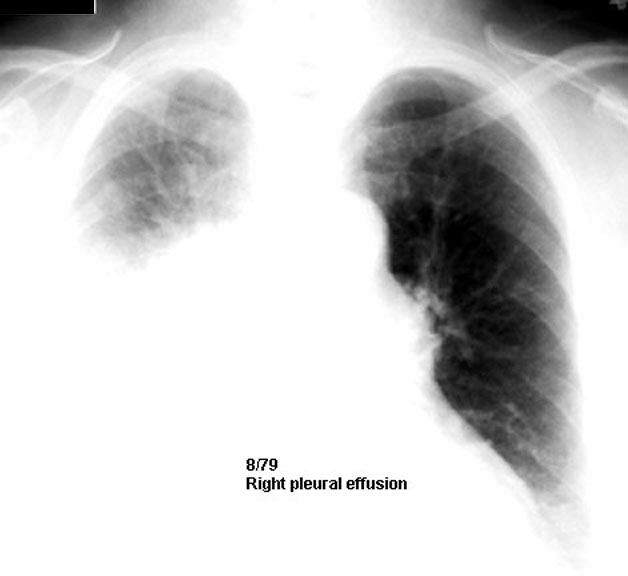

• Patient with right malignant pleural effusion

Review subsequent films below.